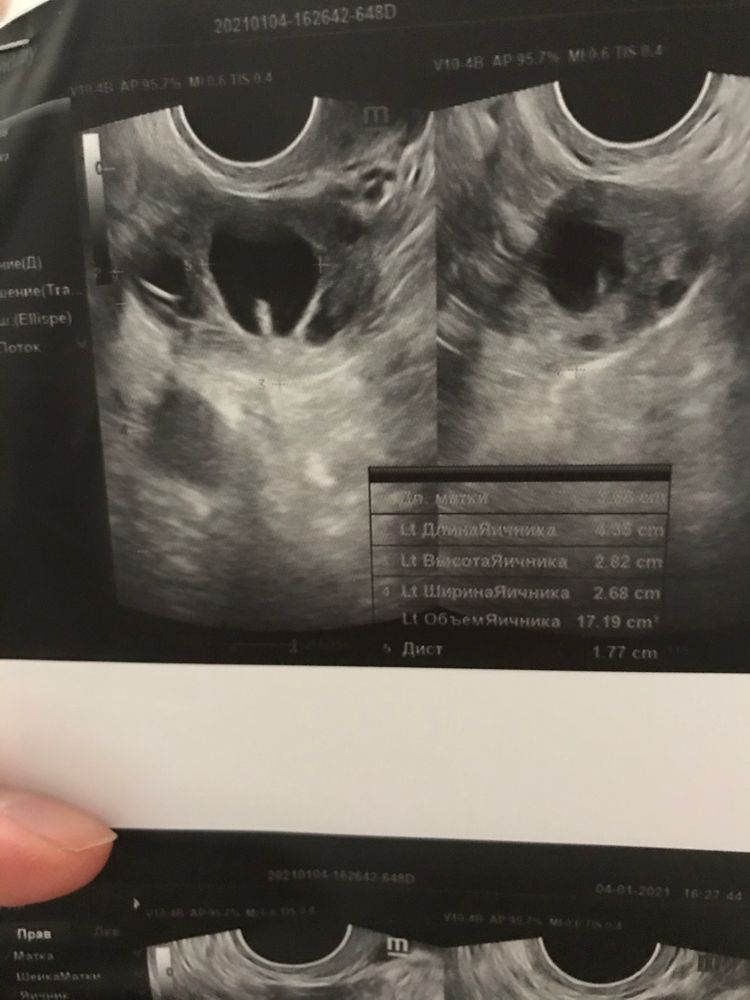

Подскажите пожалуйста, кто разбирается, 4 января на узи сказали, что желтое тело размером 18*17 мм, эндометрий 10 мм, свободная жидкость не лоцируется. Но БТ почти не растёт, 36,6-36,7. Точно ли это желтое тело?

Я по снимку не скажу, но что знаю, что ЖТ обычно имеет неровные края и должен быть виден кровоток, у ДФ края ровные как у шарика, может быть венценосный или ромбовидный бугорок, типо вот-вот лопнет в этом месте. Жидкость видна обычно первые дни, примерно до 3-4 дпо максимум.